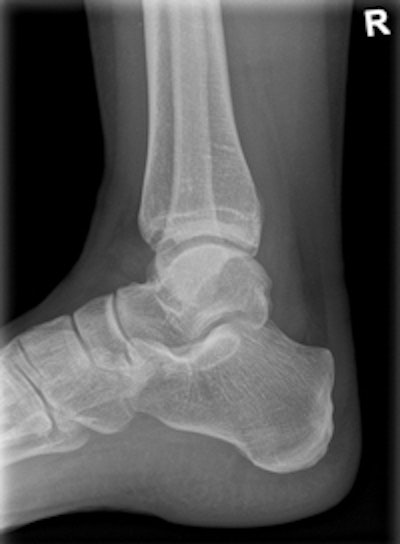

The machine can record static, dynamic, and real-time 3D sequences, and the full range of its potential applications is still to be explored. But there are clinical applications in which it already appears to have advantages over CT, notably in investigations of upper limb fractures in obese patients and weight-bearing lower-limb bone examinations of diabetics, he added.